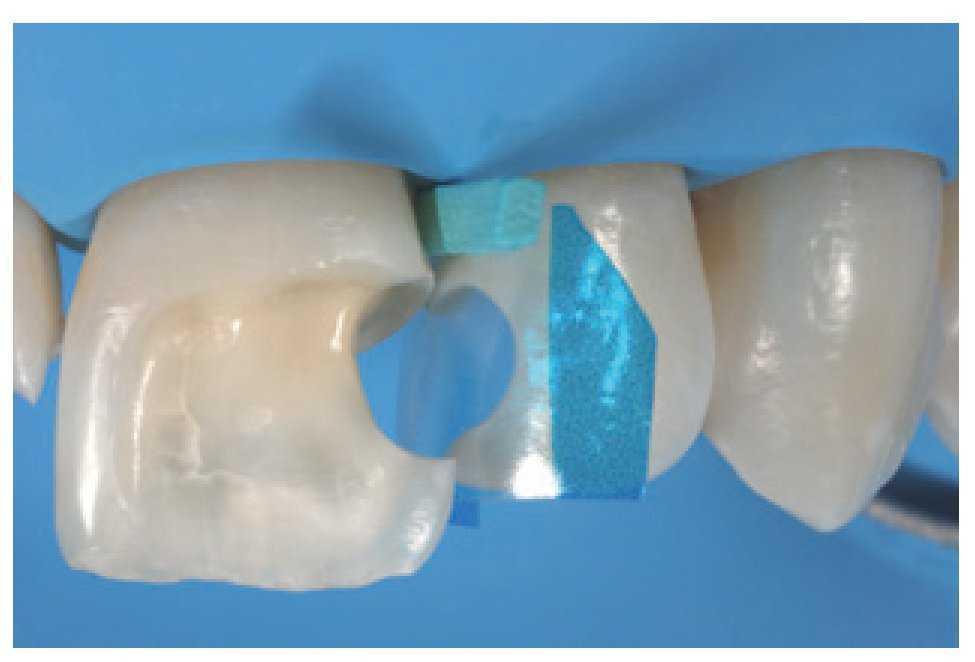

Esto es una ayuda importante, ya que consigue que el trabajo sea predecible, permite gestionar bien el tiempo y limita el tiempo de trabajo en el sillón. Asimismo, las matrices transparentes seccionales con múltiples convexidades (KerrHawe, Bioggio, Suiza) también son una ayuda útil en el manejo del tiempo, ya que permiten al clínico crear de forma sencilla e intuitiva unos perfiles de emergencia correctos. Éstas son las herramientas para gestionar de forma correcta la configuración de las restauraciones, eliminando cualquier exceso de material que conllevaría intervenciones de remodelado laboriosas y difíciles, con el riesgo añadido de dañar los dientes adyacentes y perder los puntos de contacto. Una matriz seccional es un medio útil para restaurar la anatomía interproximal gracias a su elasticidad intrínseca, que hace que sea altamente adaptable a un gran número de morfologías dentales (figuras 38 y 39). Asimismo, ayuda a evitar la contaminación accidental de los dientes adyacentes durante las fases de grabado y adhesión (figura 40). La aplicación combinada de una llave estable y matrices seccionales permite al clínico manejar de forma sencilla e intuitiva incluso las formas dentales más complejas en un único paso, optimizando así tanto el tiempo de trabajo como el resultado final (figuras 41-44).

Figura 38 Uso de una matriz seccional transparente para restaurar los perfiles de emergencia y puntos de contacto correctos.

Figura 39 Paso de estratificación, cavidad de clase III en diente número 22.

Figura 40 Uso de la matriz seccional durante la fase de grabado de la cavidad para evitar la contaminación de los elementos adyacentes.

Figura 41 Uso combinado de la llave de silicona y la matriz seccional para «encofrar» al mismo tiempo en palatino e interproximal.

Figura 44 Uso combinado de la llave de silicona y la matriz seccional para el control y la estratificación del perfil de emergencia y el punto de contacto mesial.

Asimismo, los autores sugieren aplicar matrices seccionales preformadas con múltiples convexidades en las secciones anteriores para facilitar la obtención de un perfil de emergencia natural y optimizar la posición del punto de contacto interproximal (ver caso clínico).